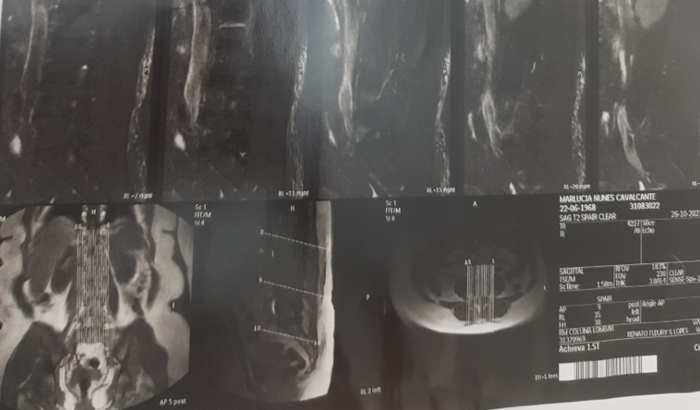

criei essa vakinha para ajudar minha mãe na cirurgia da coluna dela ,está com duas fraturas na coluna e quase não consegue andar moramos de aluguel e não temos renda peço com toda humildade e carinho quem poder ajudar que Deus te abençoe grandemente ,medico disse que tem que ser feita a cirurgia mais rapido possivel pois o caso dela e bem delicado e complicado pois ja esta inflamada a coluna dela , minha minha mãe precisa muito dessa cirurgia obrigado a todos. Todo dinheiro e bem vindo pode doar ate 1 real obrigado mais uma vez uma vez quem quiser entrar em contato manda mensagem no zap pra falar com minha mãe...